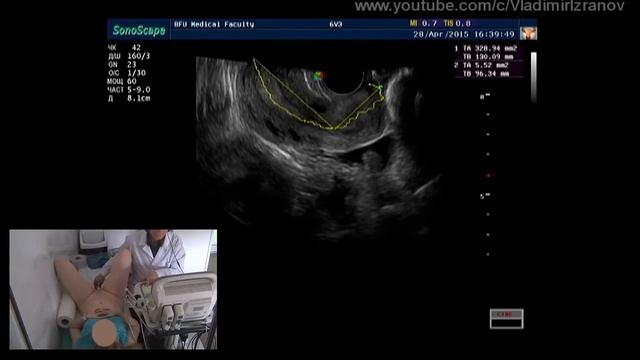

00:00 яичник в паховой грыже 00:12 гидрокольпос 00:31 апоплексия яичника 00:45 беременность раннего срока 00:57 синдром Шерешевского-Тёрнера 01:13 большая кистозная тератома имитирующая мочевой пузырь